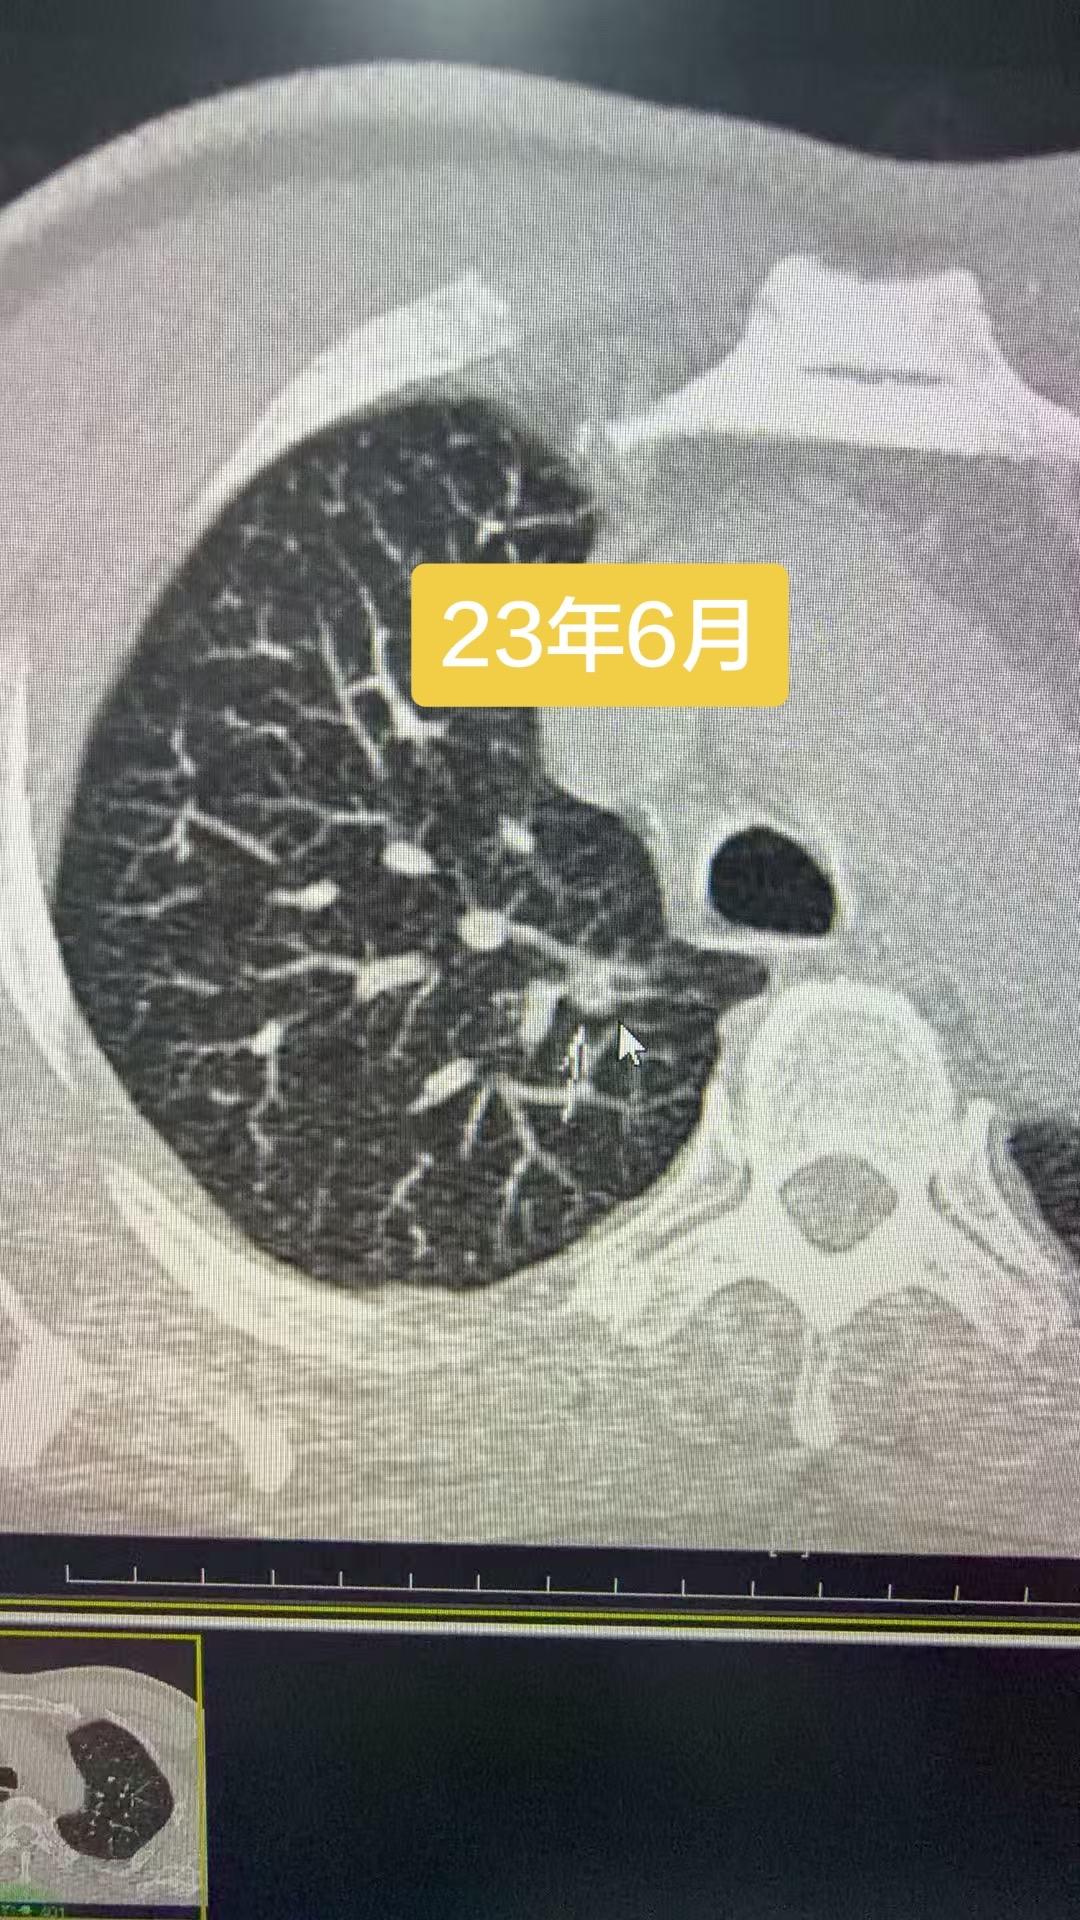

23年6月就发现的恶性结节,讳疾忌医,直接拖成晚期……猝于26年3月…...

23年6月就发现的恶性结节,讳疾忌医,直接拖成晚期……猝于26年3月……肺部结节虽然绝大多数是良性,持续增大的结节还是要重视,这个病人自己拖出大事……反面教材……